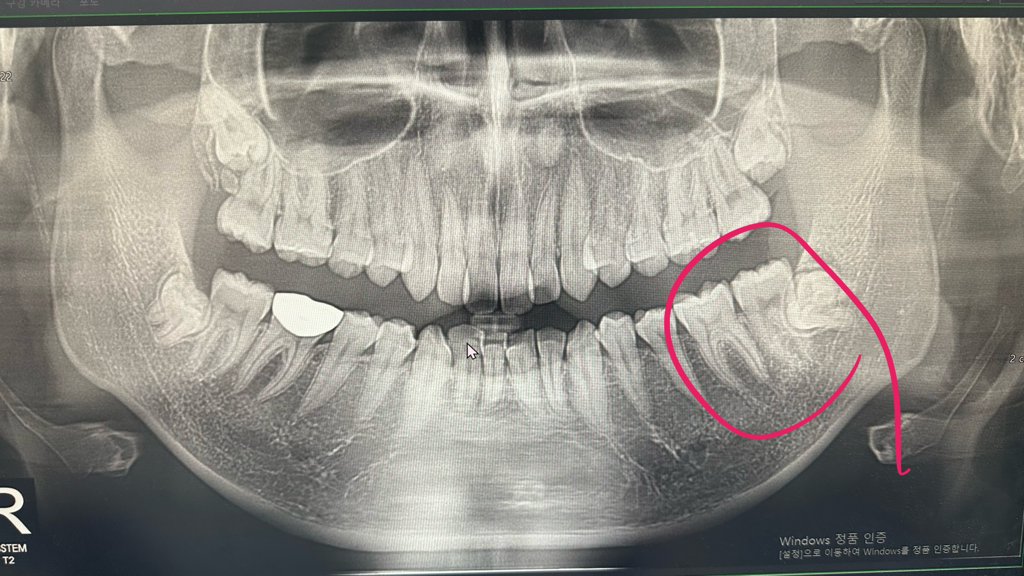

사랑니가 옆의 치아와 붙어있고 신경과도 가깝기 때문에 대학병원에서 발치를 해야겠습니다. 어렵습니다

왼쪽 아래 사랑니는 깊게 매복되어 있는 치아에다가 앞에 치아와 매우 가깝게 위치하고 있기 때문에 발치난이도가 굉장히 높은 발치입니다.

치과에서 구강 앞면 외과에서 구강 앞면의과 전문의에게 발치를 하는 것이 좋을 것으로 생각됩니다.

잇몸이 붓는 것은 해당 사랑니의 원인이 아니라 다른 원인일 수 있기 때문에 잇몸에 불편감이 있다면 정확한 원인을 확인한 후에 치료하는 것이 좋습니다.

사랑니의 매복깊이가 깊기도 하고 신경과 거리가 가까워서 대학병원 구강외과를 가셔서 발치를 하시는게 좋을것같습니다.

해당 사랑니는 완전매복 사랑니이며, 그 앞의 두번째 큰 어금니와 일부 겹쳐 있습니다. 또한 아래턱 신경관과 사랑니의 뿌리가 아주 근접합니다. 따라서 높은 난이도의 사랑니 발치라고 생각됩니다.

대학병원을 가면 좋은 이유는 만일의 사태에 대하여 빠른 협진이 가능하다는 점, CT 등 좀 더 정밀한 방사선 기기를 보유하고 있다는 점입니다.

만약 동네치과에서도 CT를 보유하고 있다면 충분히 사랑니와 신경 사이의 위치관계를 파악하여 조심하면서 발치를 시행할 수 있습니다.

다만, 파노라마 사진으로만 보면 옆 두번째 어금니에 전혀 영향을 주지 않고 발치하기는 쉽지 않을 것 같습니다.